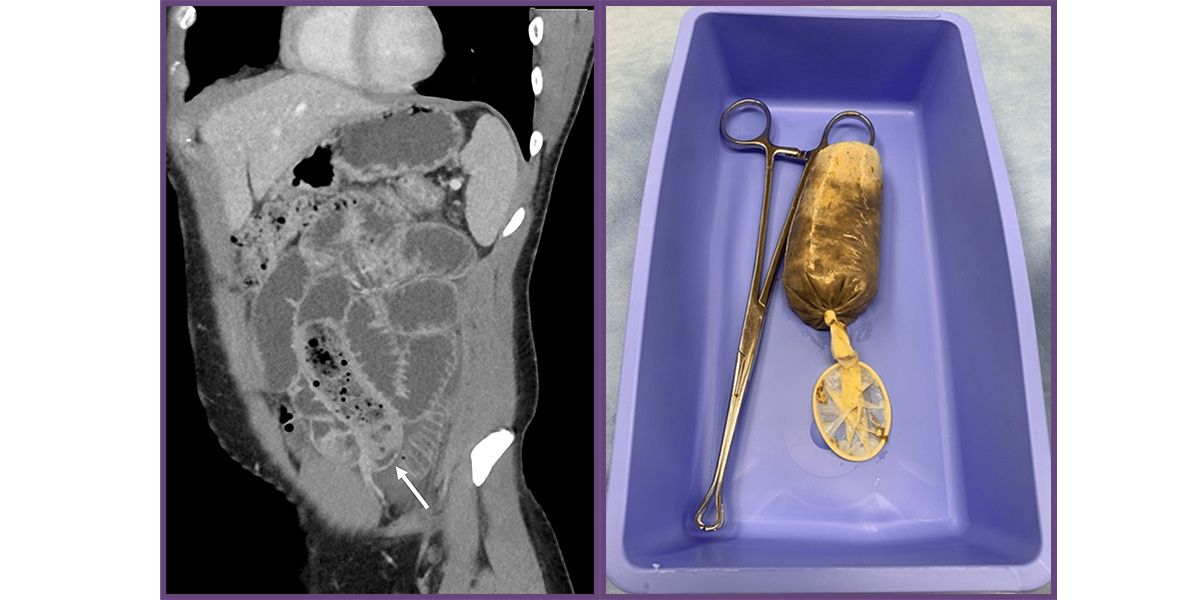

Das Beweisstück: Die Chirurgen konnten die Banane unversehrt rausoperieren.